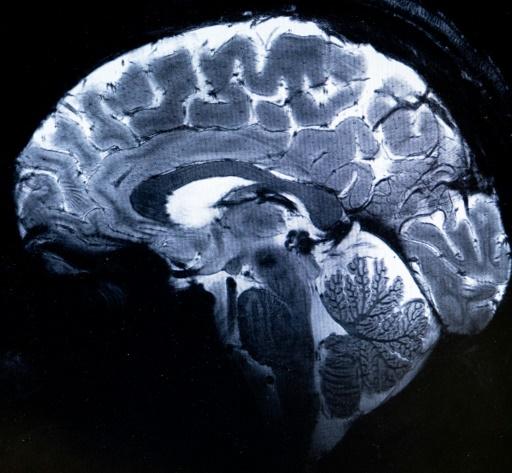

Le champ magnétique de cet aimant hors norme atteint 11,7 T (tesla), permettant l'obtention d'images 10 fois plus précises que celles produites actuellement dans les hôpitaux, où la puissance des IRM ne dépasse pas 3 tesla.

Sur l'écran d'Alexandre Vignaud, des images de coupes de cerveau sont comparées avec ce qu'aurait donné un IRM de 3 ou 7 tesla: "Avec cette machine, on peut voir les tout petits vaisseaux qui alimentent le cortex cérébral ou des détails du cervelet qui étaient quasi invisibles jusqu'alors", commente-t-il.